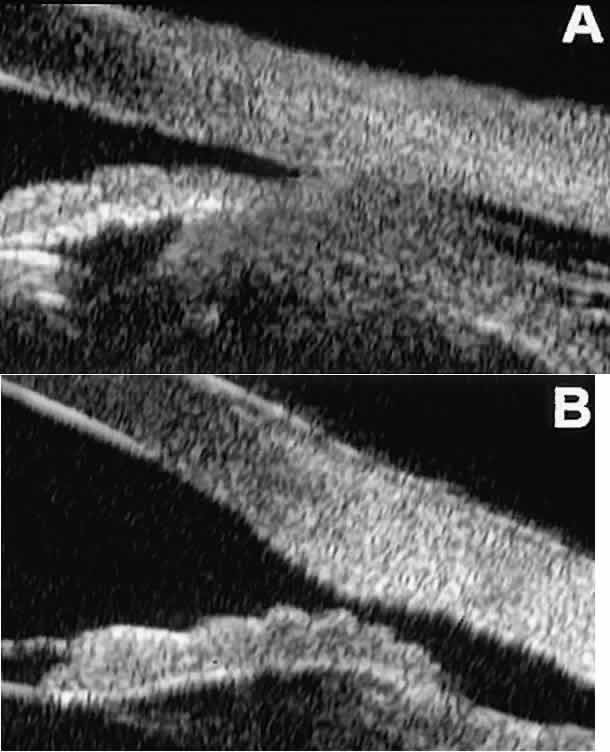

In open-angle glaucoma, UBM can be used to measure the anterior chamber angle in degrees, to assess the configuration of the peripheral iris, and to evaluate the trabecular meshwork (Fig. 9).2,4 The angle configuration can be graded and compared with gonioscopic findings. In certain patients with open-angle glaucoma, UBM can provide information that may be of some diagnostic value (Fig. 10). For example, in pigment dispersion syndrome (see Fig. 10A),6 UBM typically reveals posterior bowing of the peripheral iris (“q” configuration of peripheral iris by Spaeth classification5). In plateau iris syndrome (see Fig. 10B),7 UBM usually reveals abnormally steep anterior angulation of the peripheral iris (“s”configuration of peripheral iris by Spaeth classification5), insertion of the iris from the anterior ciliary body, and retroiridic projection of the ciliary processes. In eyes with peripheral anterior synechiae (see Fig. 10C and D), UBM can reveal the extent of iridocorneal adhesion even if the cornea is hazy or opaque.

Fig. 9. Angle configuration in eyes with open-angle glaucoma. A. Wide open angle with flat iris plane (D40r configuration by Spaeth gonioscopic grading system). B. Moderately wide angle with anteriorly bowed iris plane (C30r by Spaeth gonioscopic grading system).

Fig. 10. UBM features of special glaucoma cases. A. Pigment dispersion syndrome with posterior bowing of peripheral iris (“q” configuration by Spaeth gonioscopic grading system). B. Plateau iris syndrome with origin of iris from anterior surface of ciliary processes behind peripheral iris, slitlike narrowing of peripheral angle, and abrupt transition from steep peripheral iris to flat iris midzone. C. Broad peripheral anterior synechia with posterior bowing of nonadherent iris. D. Peripheral anterior synechia with aqueous-filled slit between site of iridocorneal adhesion and iris root after cataract extraction with implantation of posterior-chamber IOL.